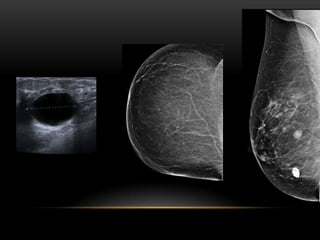

NODULOS EN O SOBRE LA PIEL

NODULOS EN OSOBRE LA PIEL